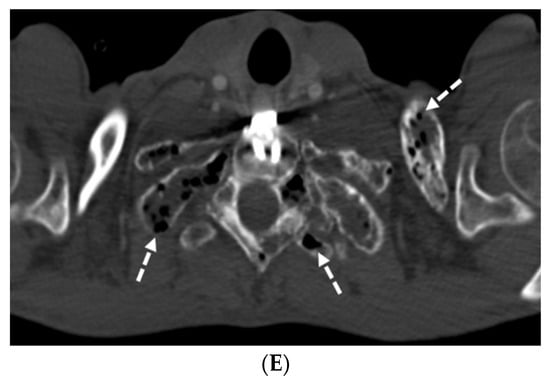

6.1. Coal Worker’s Pneumoconiosis (CWP)

| Coal worker’s pneumoconiosis (CWP) | Exposure to coal dust free of silica | No specific findings |